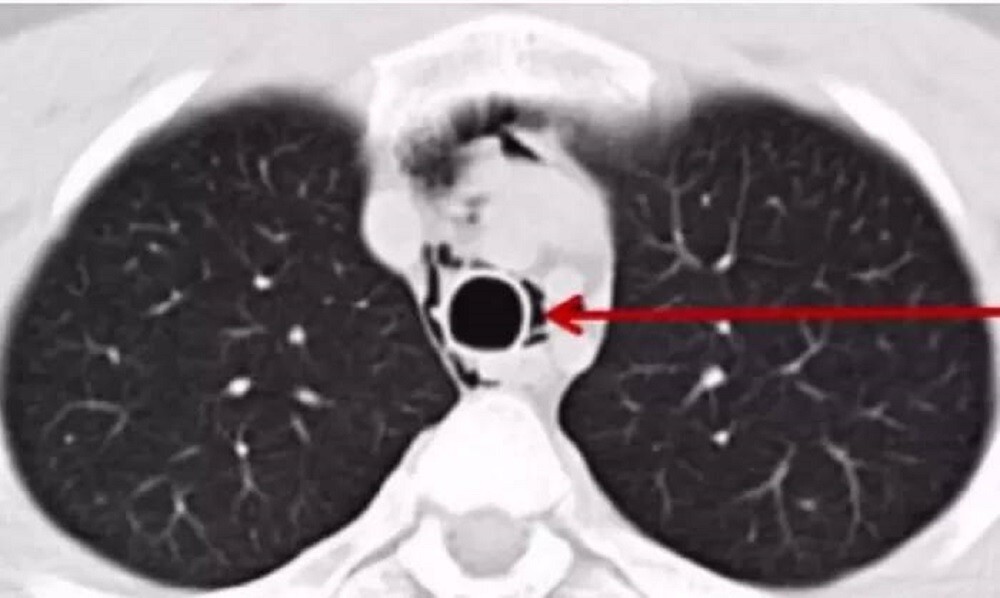

When the guy was taken to the hospital, the doctors diagnosed rupture of the alveolar process in one of the lungs due to excessive screaming during a concert, according to Oddity Central.